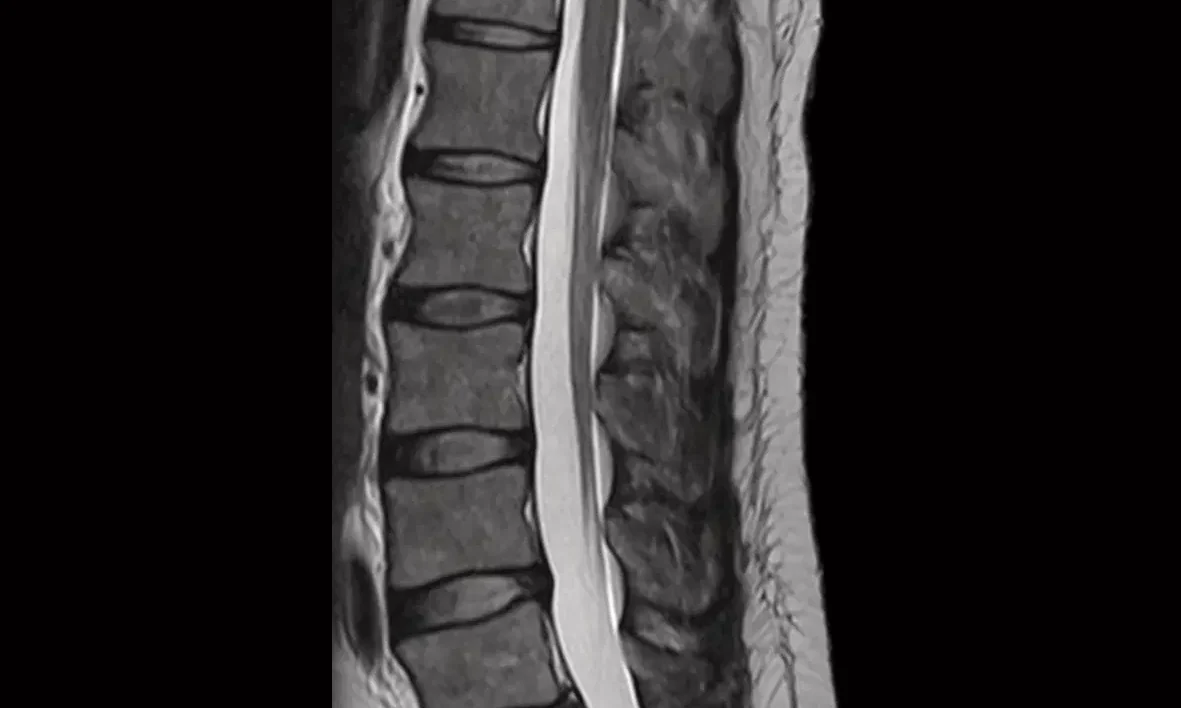

Brain / Pituitary / IACs / Orbits / DTI / Abdomen / Pelvis / Face / Soft Tissue / Breast / Prostate / C-Spine / T-Spine / L- Spine / All Extremities / Whole Body MRI Whole Spine MRI (includes C, T, L-Spine)